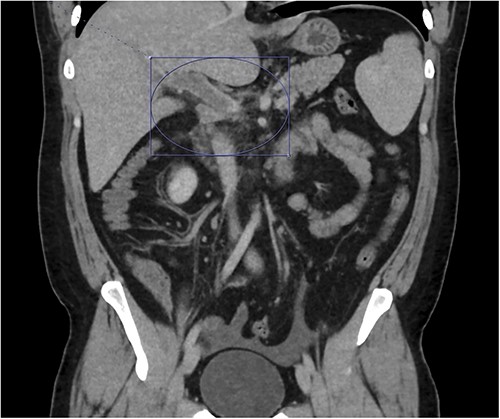

On presentation to the emergency department (ED), he was afebrile and normotensive with blood pressure in the 120s/80s though he had sinus tachycardia (heart rate 120–130 s). His abdomen was soft and diffusely tender with point tenderness at McBurney’s point and negative Rovsing’s sign. He had no signs of frank peritonitis. His complete blood count revealed leukocytosis (WBC 11K/μl), lactic acidosis (lactate 3 mmol/l), and mild transaminitis with AST 72 and ALT 101. An intravenous (IV) contrast-enhanced computed tomography scan of the abdomen/pelvis demonstrated a mildly dilated appendix (~8 mm) with surrounding fat stranding but no appendicolith, perforation, or abscess (Fig. 1). Interestingly, a partial portal vein (PV) and superior mesenteric vein (SMV) thrombosis were also noted (Fig. 2). Initial blood cultures were collected, which remained without growth.

A hyperemic and inflamed appendix can be seen without an abscess, perforation, or appendicolith.